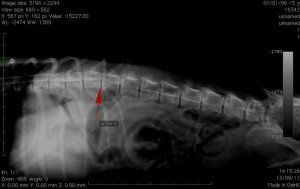

Radiographie de la colonne vertébrale:

En cas de difficultés locomotrices, il est possible de repérer des lésions des vertébrales. sur une radio sans préparation. L’injection de produit de contraste dans la colonne vertébrale (myélographie) est parfois nécessaire pour visualiser d’éventuelles compressions de la moelle épinière (hernies discales) qui peuvent être responsables de paralysies chez votre animal.